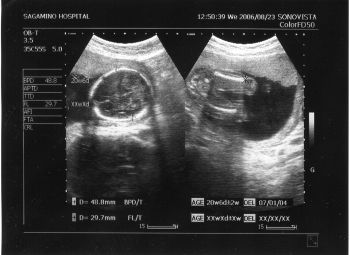

| 2006-06-07 初エコー | 2006-08-04 日本で | |